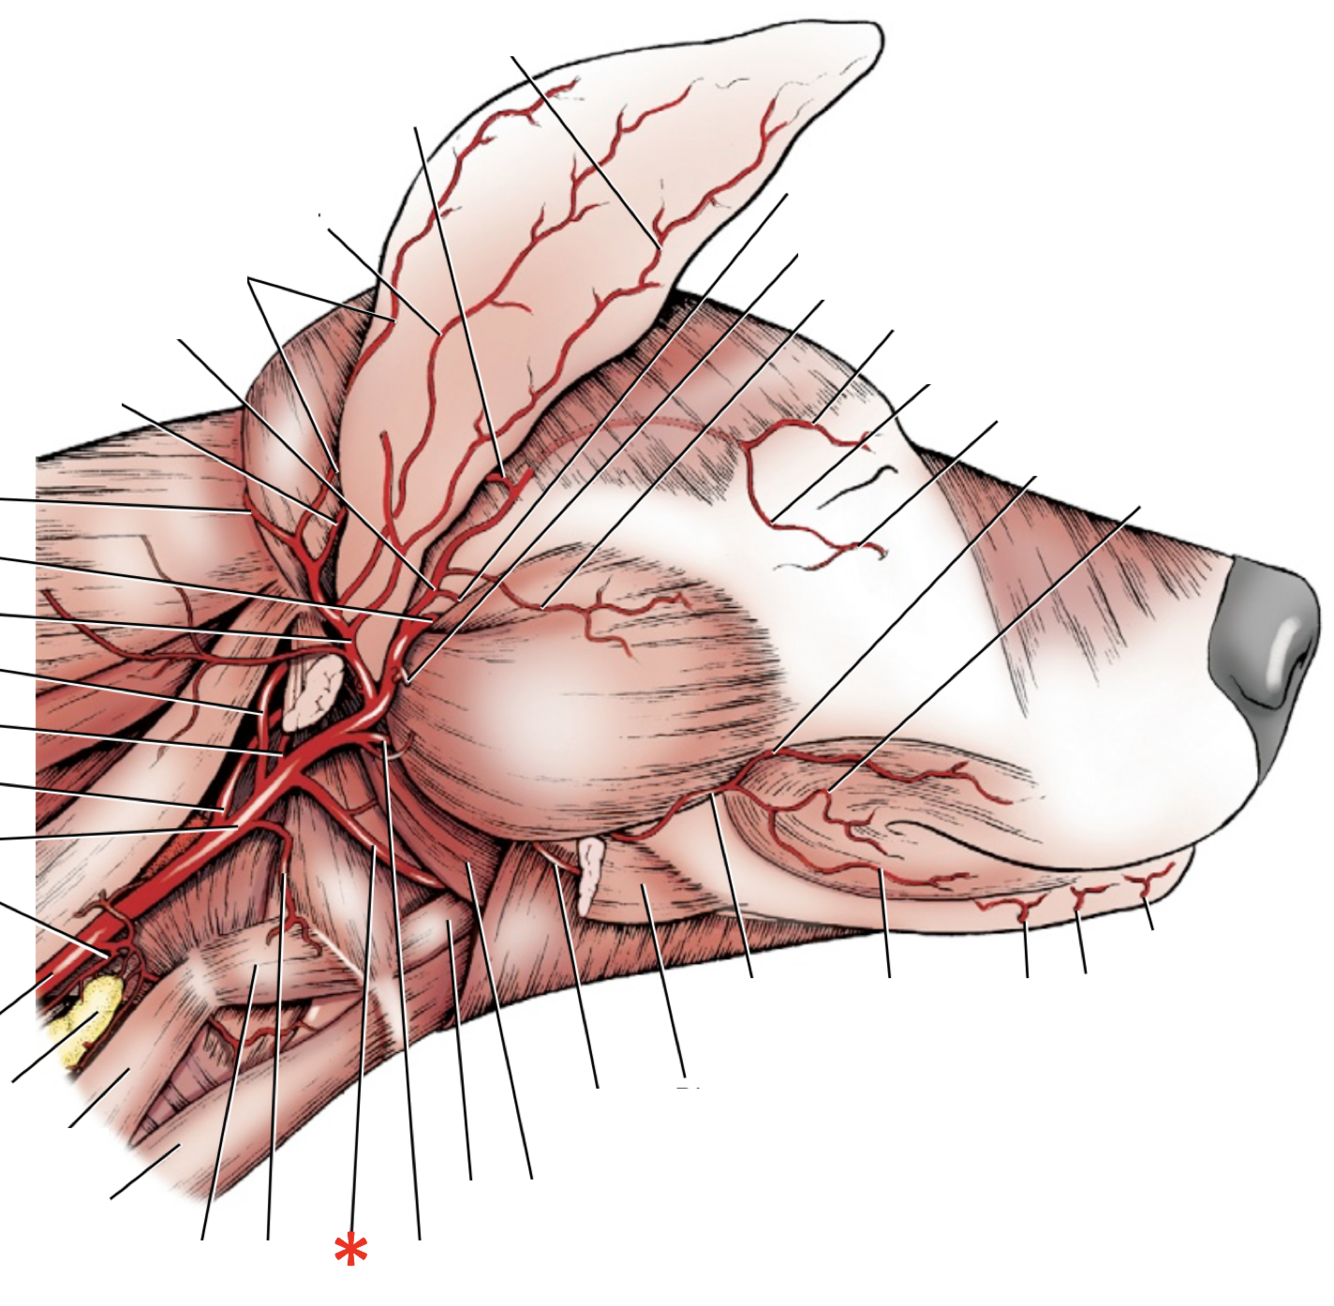

1

Q

A

A. lingualis

2

Q

A

A. facialis

3

Q

A

A. maxillaris

4

Q

A

A. auricularis caudalis

5

Q

A

A. occipitalis

6

Q

A

A. sublingualis

7

Q

A

A. temporalis superficialis

8

Q

A

A. facialis

9

Q

A

A. cariotis externa

10

Q

A

A. maxillaris